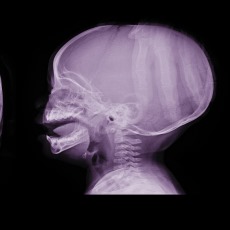

Hydrocephalus is the buildup of too much cerebrospinal fluid in the brain. Normally, this fluid cushions your brain. When you have too much, though, it puts harmful pressure on your brain.

Hydrocephalus can be congenital, or present at birth. Causes include genetic problems and problems with how the fetus develops. An unusually large head is the main sign of congenital hydrocephalus.